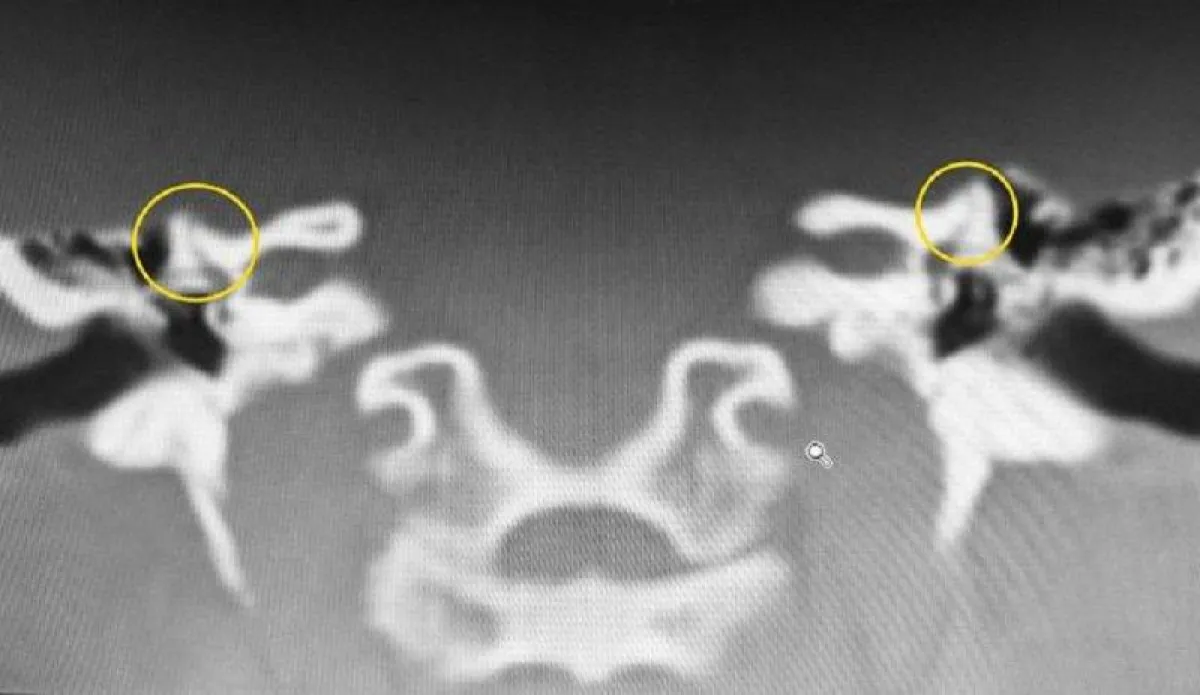

وتابعت «ميرور»، أن جيما التي تعيش في مدينة «غلاسكو» في أسكتلندا، قررت في نهاية الأمر أن تتعايش مع حالتها بأي شكل من الأشكال. حتى جاء العام 2016، وأخبرتها إحدى الطبيبات الإخصائيات، أنها تعاني من فشل في «القناة الهلالية»، أي أن جزءاً من العظم الصدغي في كل من قنوات أذنيها غير موجود، وهو الأمر الذي يؤثر على توازنها بشكل عام، وعلى سمعها تحديداً.